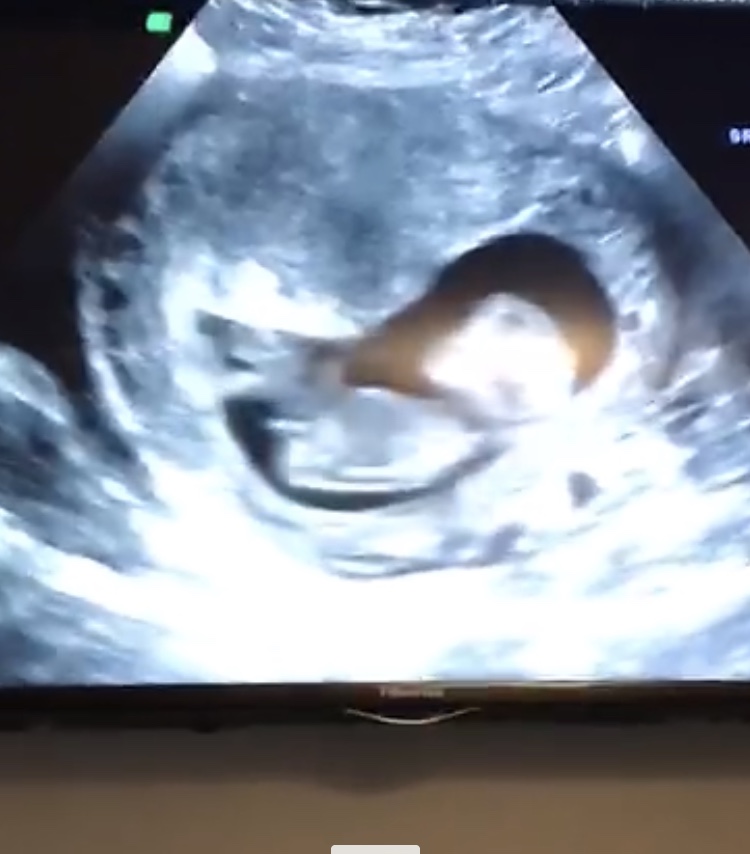

Hi ladies! Baby wouldn’t lie flat, kept curling up/sitting up so I’m not sure how to interpret the nub here. Would love any guesses :)

I'm leaning blue with this pic alone. Potty shots at this gestation aren't recommended to go off of but with all my boys I could see a dangly there at 12+ wks!

I'd actually lean pink on this one just because the nub looks long and forked. Baby is curled up though so I'm not confident. It's still early so potty shots aren't reliable at all at this gestation.

Ok went back through the short video of the scan my husband took (went a little Macguyver 😂 ). Screen shot shows the back a bit flatter. Does this help? You ladies are the best.

Girl guess